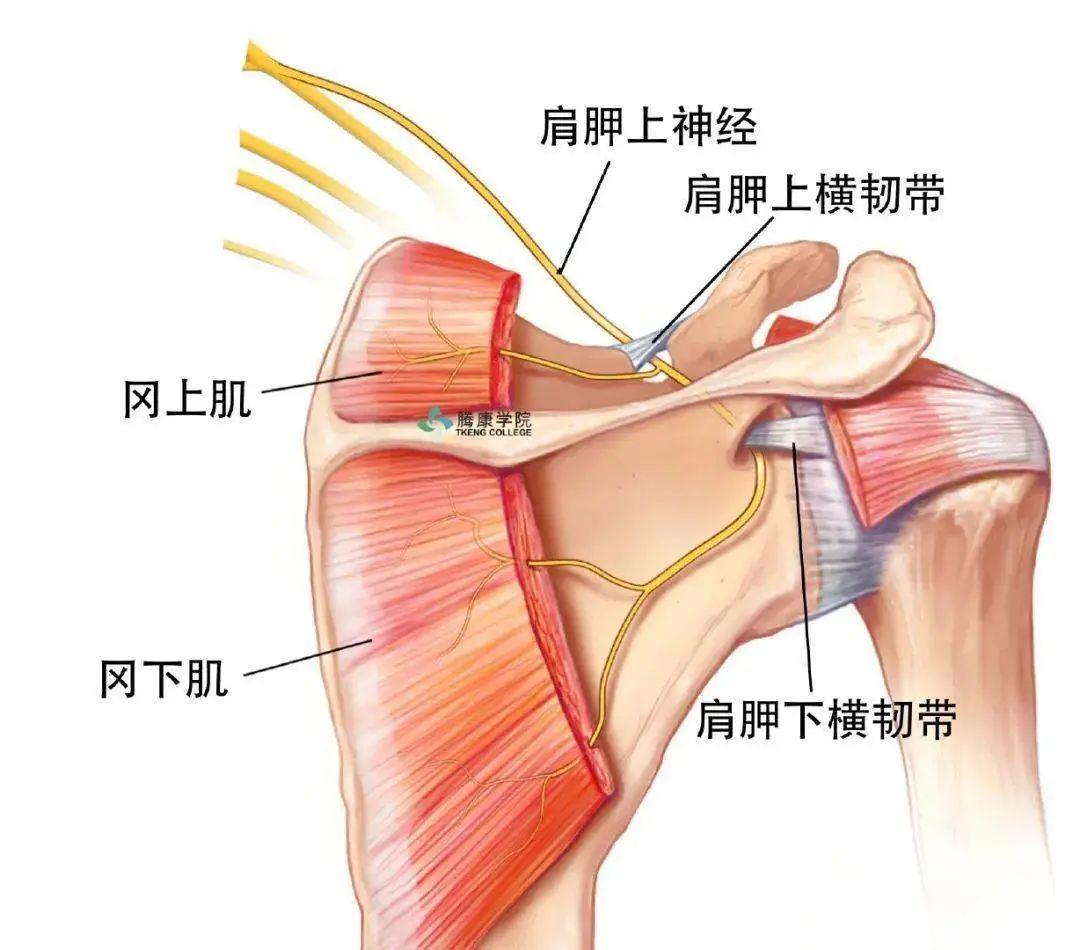

肩胛上神经卡压综合征

因肩胛骨骨折或盂肱关节损伤等急性损伤或慢性肌肉损伤所致,局部肿胀使肩胛上神经卡压,常有肩周区弥散的钝痛,位于肩后外侧部,可向颈后及臂部放射,但放射痛常位于上臂后侧。患者常感肩外展、外旋无力。

局部肌肉劳损或急性损伤

冈上肌、三角肌的慢性积累性损伤或者急性损伤导致的局部疼痛,相关肌肉主动运动时疼痛明显,休息好转。